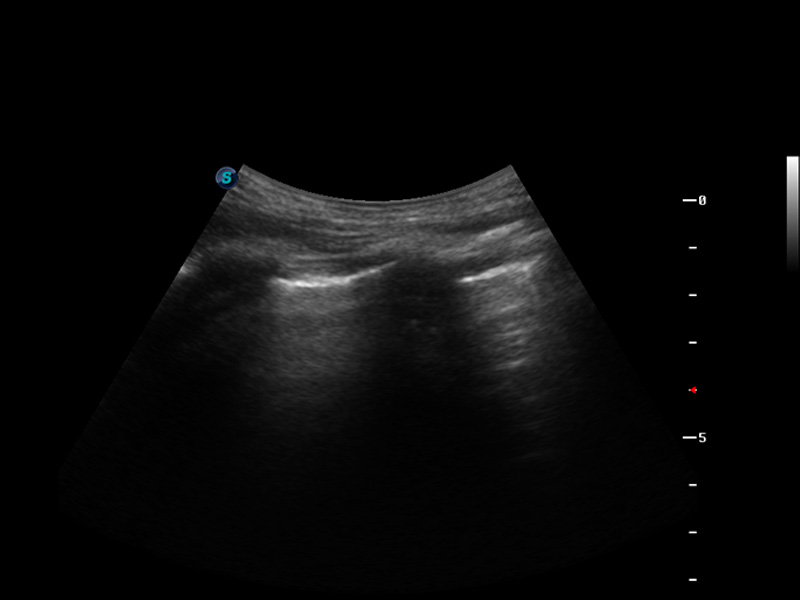

S9便携式彩色多普勒超声诊断仪是16877太阳集团研发的高端便携彩超设备,外观设计新颖、产品性能卓越。S9在便携超声领域采用了突破传统的触摸屏交互设计,并以先进的软件硬件技术和设计理念,为您带来清晰的图像质量、稳定的工作性能和便捷的操作体验。

脉冲反相谐波成像